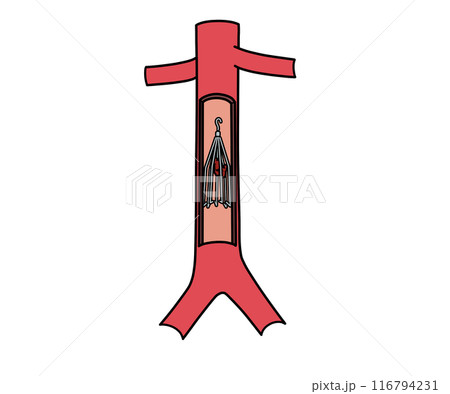

末梢血管疾患解説患者さまへイムス葛飾ハートセンタ。

血管外科 下肢静脈瘤・むくみ 西川口きむら内科外科クリニック 下肢静脈瘤 胃カメラ。

上皇后さまが発症された深部静脈血栓症について解説します下肢静脈瘤の原因・症状・治療方法・予防方法などを専門医が解説。

脚領域における深部静脈血栓症の医学的図。のイラスト素材・ベクター Image 98030310。

深部静脈血栓症 DVT の病態と予防見て!わかる!病態生理と看護 花子のまとめノート。

深部静脈血栓症 - 血栓のベクターアート素材や画像を多数ご用意 - 血栓, 肺塞栓症, イラストレーション - iStock。

深部静脈血栓症、血栓症。塞栓。正常静脈と静脈瘤の構造。イラストは私が作成しました写真素材1443942500Shutterstock。